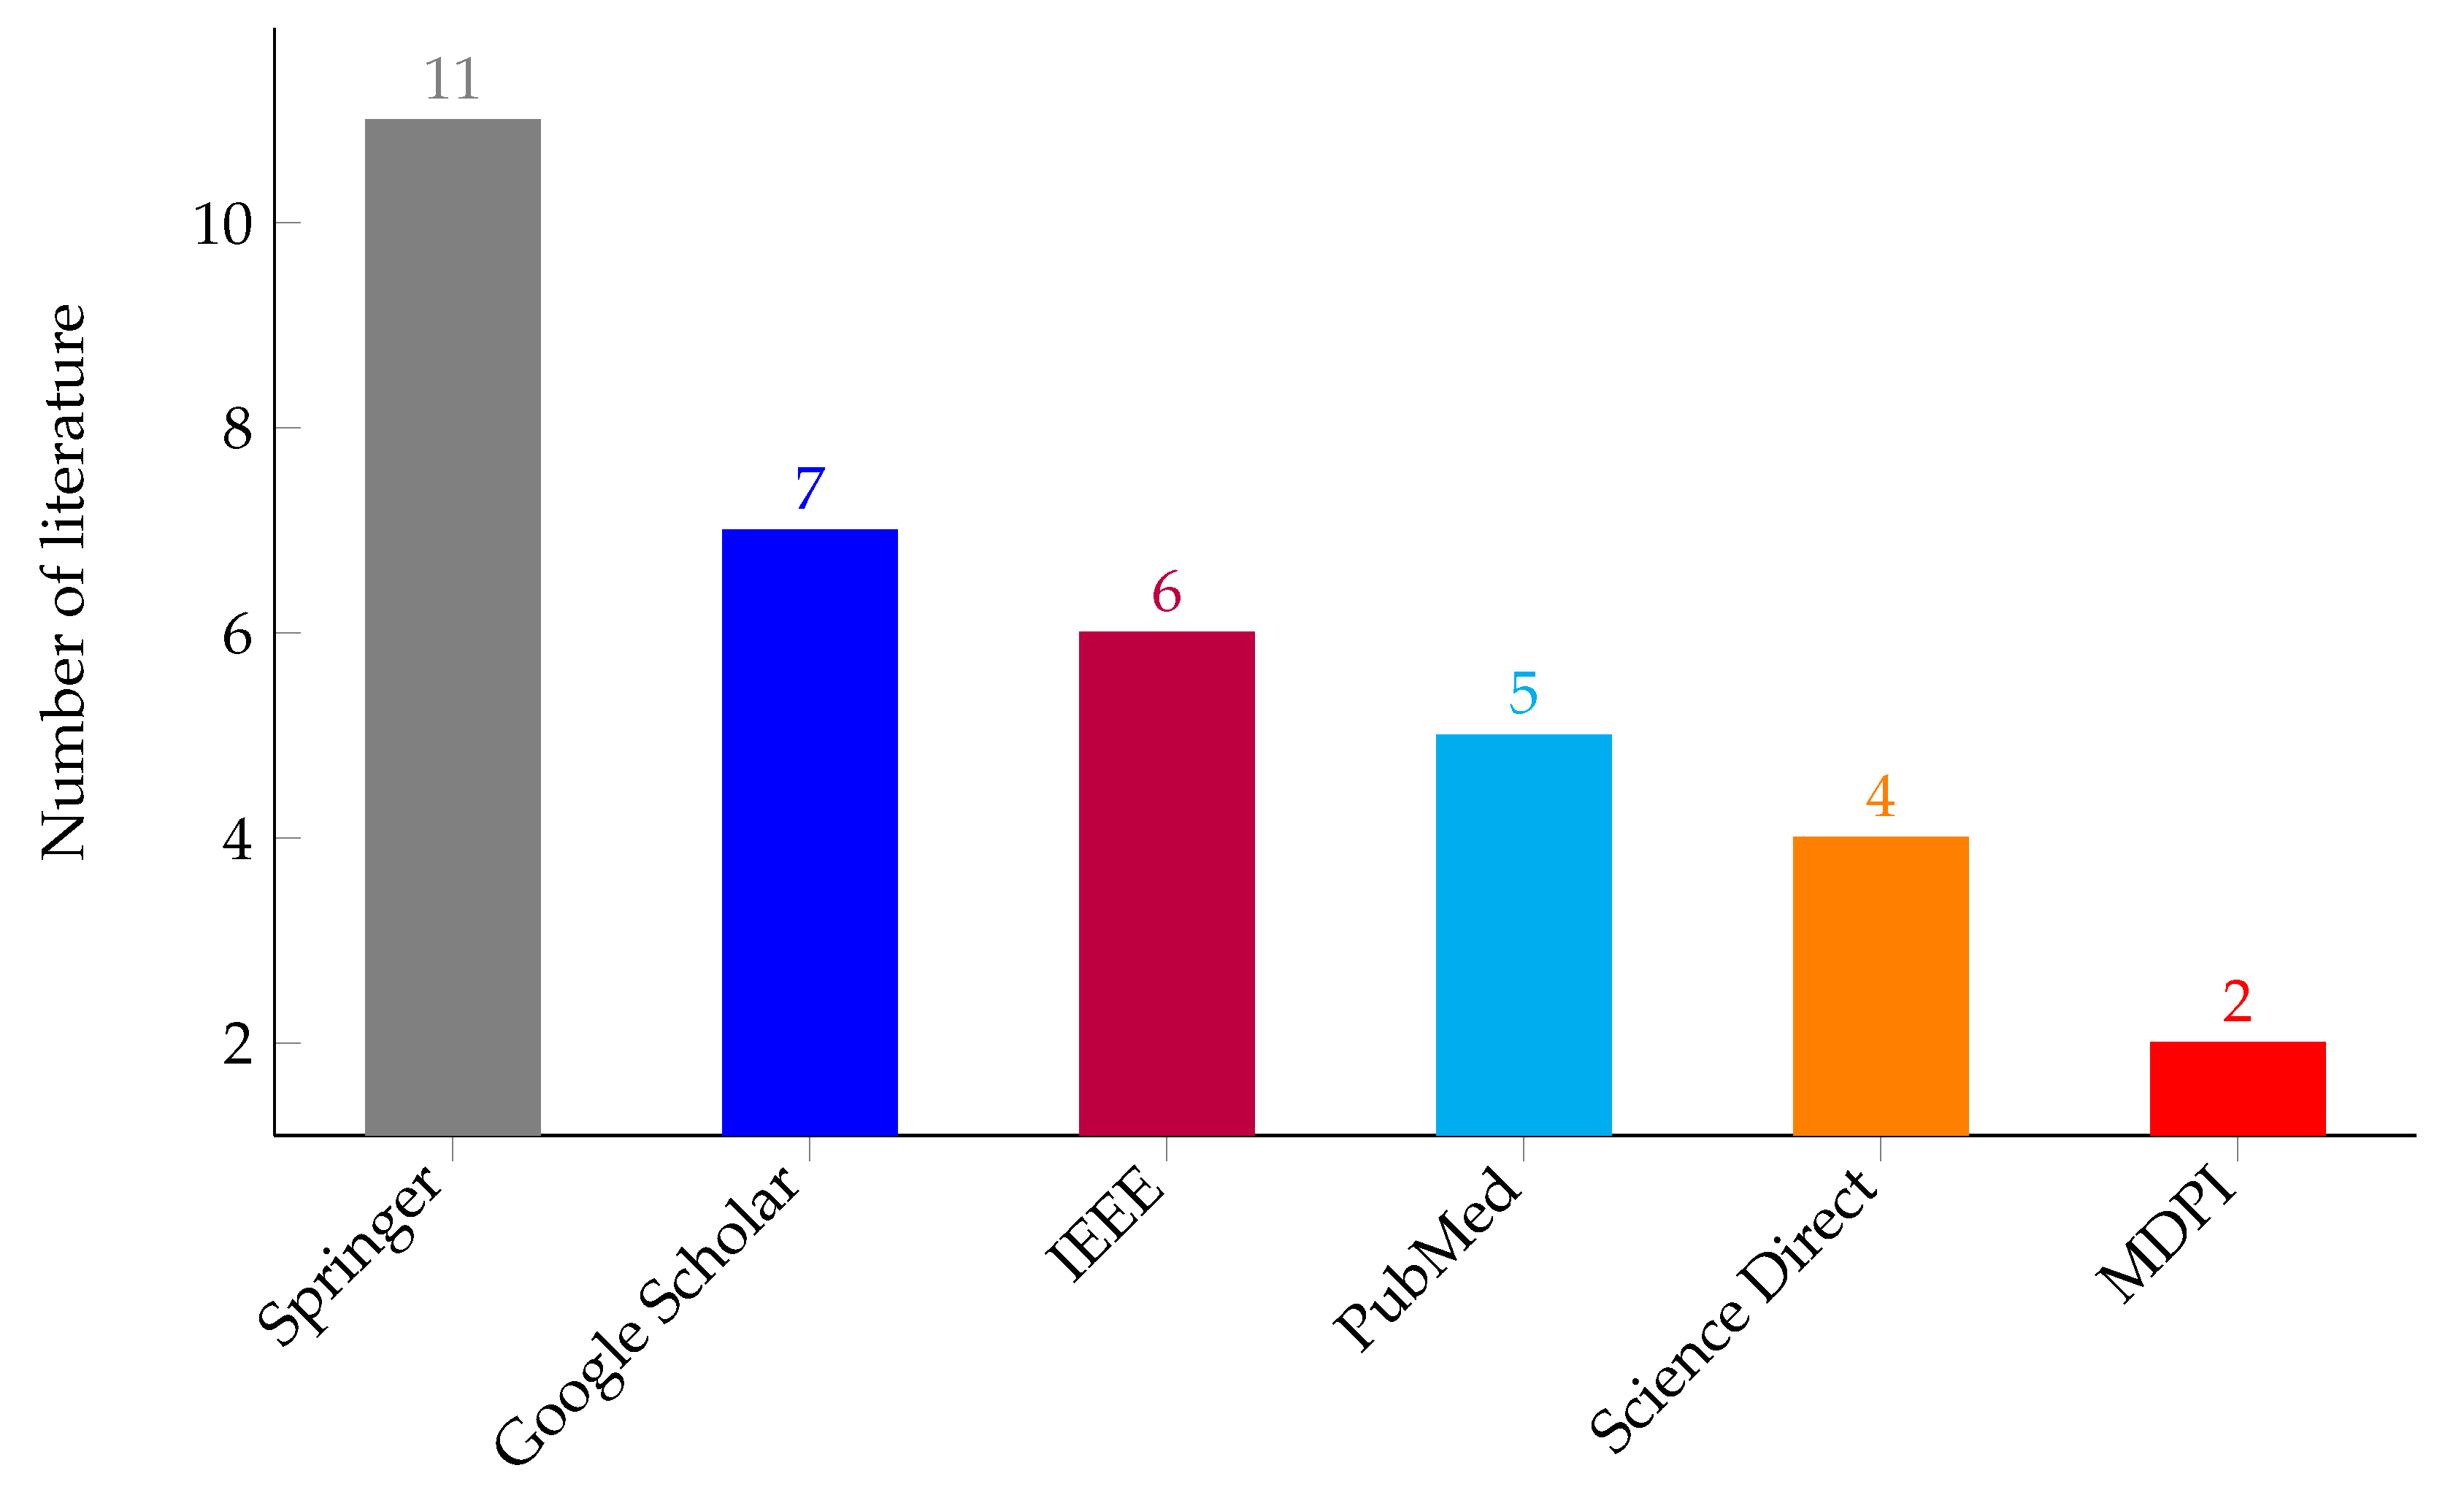

3.2. Search Strategies